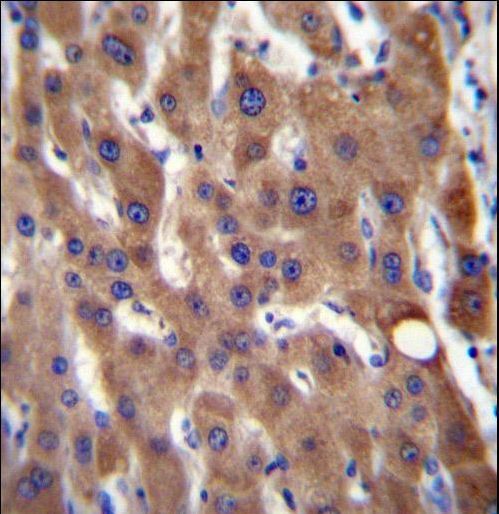

Supportive validation

- Submitted by

- LSBio (provider)

- Enhanced method

- Genetic validation

- Main image

- Experimental details

- CIB4 Antibody immunohistochemistry of formalin-fixed and paraffin-embedded human liver tissue followed by peroxidase-conjugated secondary antibody and DAB staining.